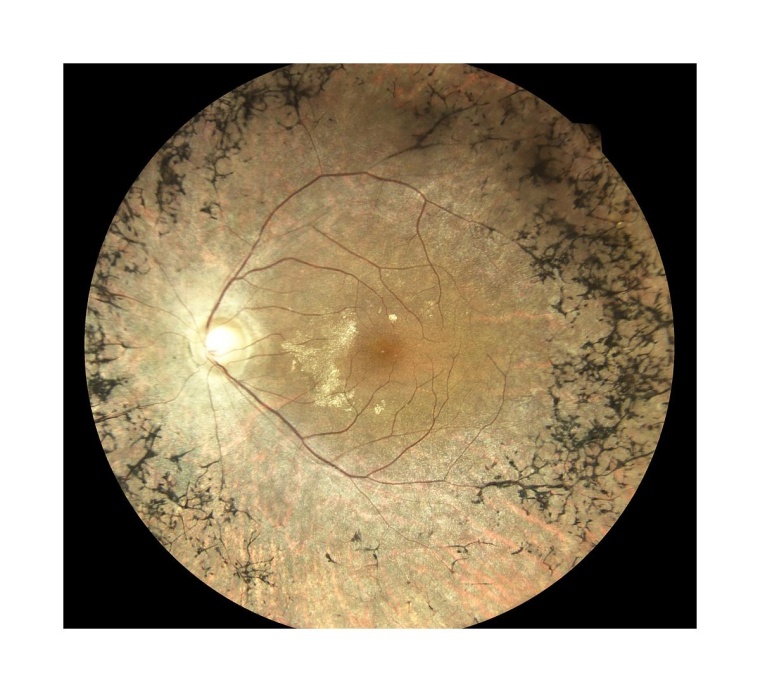

Der wissenschaftliche Fokus der Bonner Sprechstunde für seltene Netzhauterkrankungen liegt neben innovativen, hochauflösenden Bildgebungsverfahren insbesondere auf neuen Therapieansätzen, wie der Gentherapie bei Retinitis pigmentosa. „Wir führen zahlreiche klinische Studien bei seltenen Netzhauterkrankungen durch und sind eines der drei deutschen Behandlungszentren für die neu zugelassene Genersatztherapie mit Luxturna“, so Frau Prof. Birgit Lorenz, Senior Medical Expert an der Bonner Augenklinik. Die Ärzte haben in den letzten beiden Jahren 18 Patienten mit diesem neuen Verfahren behandelt und sind damit das größte deutsche Behandlungszentrum und auch international eines der größten Zentren für diese erstmals zugelassene Therapie. Neben der Gentherapie gibt es noch zahlreiche weitere Ansätze. Diese reichen von pharmakologischen Ansätzen bei Morbus Stargardt über die Implantation von Bioreaktoren in das Auge bei Makulären Teleangiekasien Typ 2 bis hin zu elektronischen Chips zum Ersatz zugrundgegangener Netzhaut.